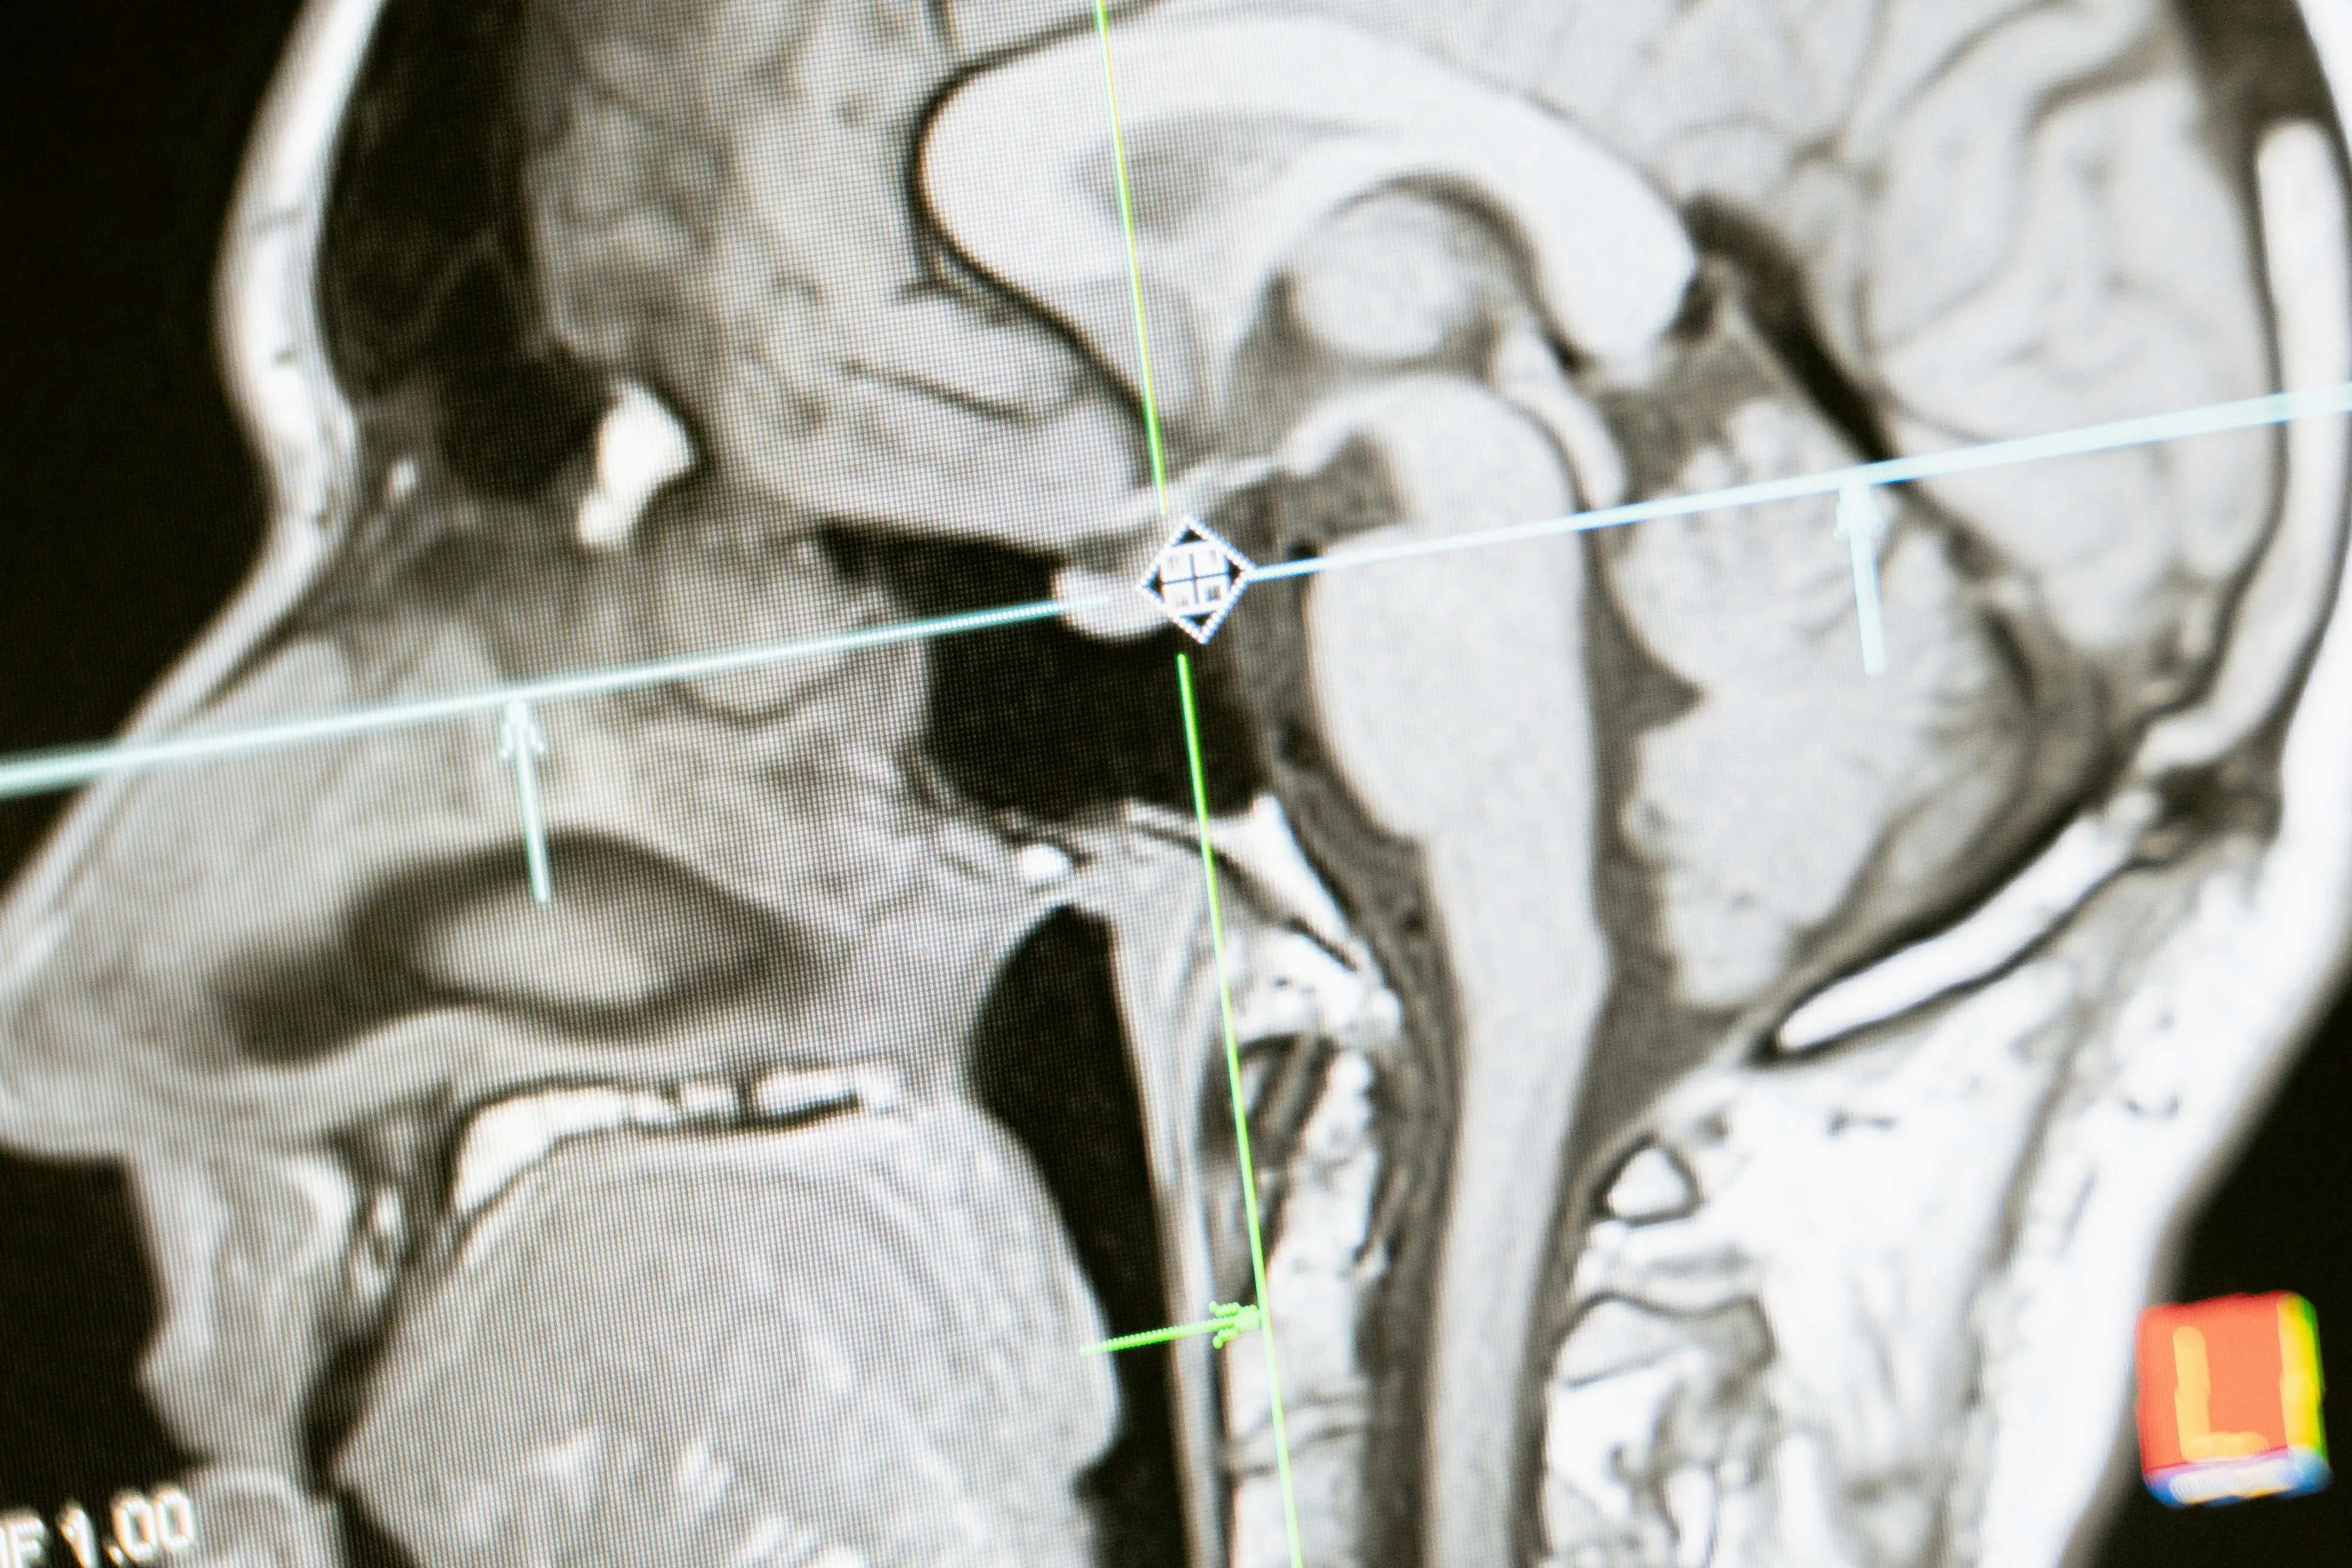

조기 치매는 노인성 치매보다 진행이 빠르고 증상도 다양해서 정확한 진단이 필요하다. 기억력 감퇴나 언어 장애 등 인지기능 저하가 일상에 지장을 준다면 전문적인 상담을 받아야 한다.